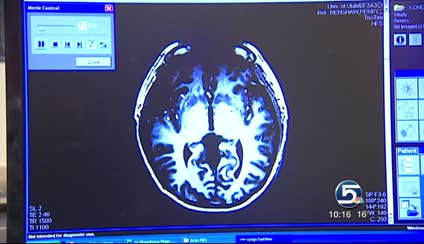

In before and after brain scans of patients, graphs show some dramatic differences. Those images are documented by a sophisticated MRI at the Imaging and Neurosciences Center. As displayed in peaks and dips, the spikes of phosphorus creatine levels are much lower in those with depression or bipolar illnesses.

As Renshaw describes, "The higher the brain's level of phospho-creatine, the more likely you are to get better if you are depressed."